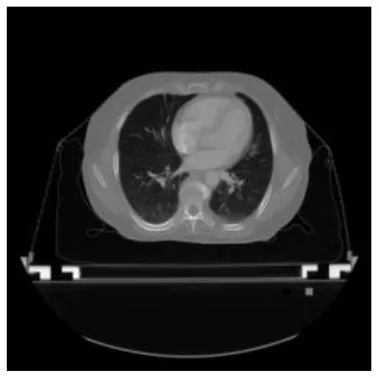

According to the acquired model parameters mentioned above, the testing set was calculated and examined. The performance of the modified algorithm for automatic organ segmentation in CT images is shown in Table 1. The organ contours segmented automatically by the algorithm were similar to those delineated by physicians manually. The model parameters including DSC, Accuracy, Recall, and Precision evaluation ones were served to evaluate the segmentation effectiveness of each organ in the validation and testing sets. In our work, the BCDU-Net CNN algorithm model was used to automatically segment different organs with the different training parameters such as epoch learning rate. The CT images which were randomly selected from the patients were put into the network model for training, and then the contours of different organs which were delineated automatically by the AI technology and manually by medical doctors were evaluated with the similarity coefficients, respectively. The results are given in Table 2. Most of the DSC values were better than 0.85 and among them the best even reached up to 0.9676. Generally, the automatic segmentation results met the requirements of clinical practice.

| Input CT image | Organs with manual segmentation | Organ with automatic segmentation | |

| Bladder | ![]() | ![]() | ![]() |

| Brainstem | ![]() | ![]() | ![]() |

| Eye-L | ![]() | ![]() | ![]() |

| Eye-R | ![]() | ![]() | ![]() |

| Femur-L | ![]() | ![]() | ![]() |

| Femur-R | ![]() | ![]() | ![]() |

| Heart | ![]() | ![]() | ![]() |

| Intestine | ![]() | ![]() | ![]() |

| Kidney-L | ![]() | ![]() | ![]() |

| Kidney-R | ![]() | ![]() | ![]() |

| Liver | ![]() | ![]() | ![]() |

| Lung-L | ![]() | ![]() | ![]() |

| Lung-R | ![]() | ![]() | ![]() |

| Mandible | ![]() | ![]() | ![]() |

| Rectum | ![]() | ![]() | ![]() |

| Spleen | ![]() | ![]() | ![]() |

| Stomach | ![]() | ![]() | ![]() |

The result of manual and automatic organ segmentation.